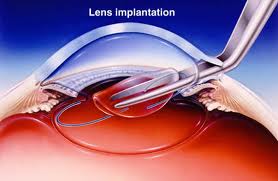

Phaco emulsification (Stitch less cataract surgery) With Intraocular Lens Implantation

cataract surgery is done to remove cloudy lens and replace it with latest intraocular lenses.

LENS BEING IMPLANTED

In this surgery the cataractous lens is broken down into small pieces with the help of ultra sound energy and sucked out. The operation is done through a < 1 mm to 2.8 mm small tunnel incision so that after operation no stitches are required because incision is self sealing. Intra ocular lens is also implanted through the same incision. The foldable lenses are used these days. These lenses get folded and are loaded in a plastic injection. The lens is then injected into the eye through the small incision made for surgery.